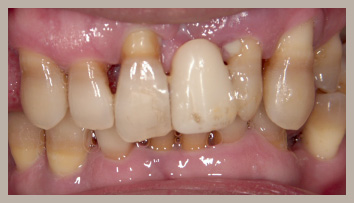

【歯周病重度】

歯肉の炎症はますます進み、赤くブヨブヨとした歯肉になります。それと同様に歯周組織の破壊も加速し、歯の支持している骨が破壊され、歯を支持する骨が少なくなります。

歯肉は若干退縮しますが、歯周病重度でも進行に気づきにくい場合もあります。ブラッシング時には、出血だけでなく膿が出ることもあり、また、強い口臭などの症状も認められます。歯周ポケットの深さは5mm以上になります。